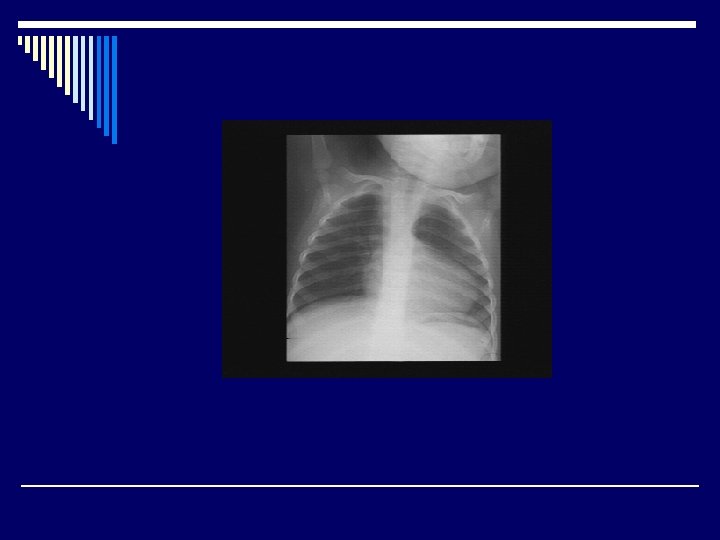

Chest X-ray o. Normal-sized boot shaped heart ( RV prominence + concavity at PA) o. Decreased pulmonary vascular markings o. Right-sided aortic arch